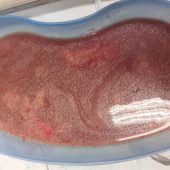

Einige Bilder zu dieser Odyssee:

- Diese Flüssigkeit war in den Umfangsvermehrungen.